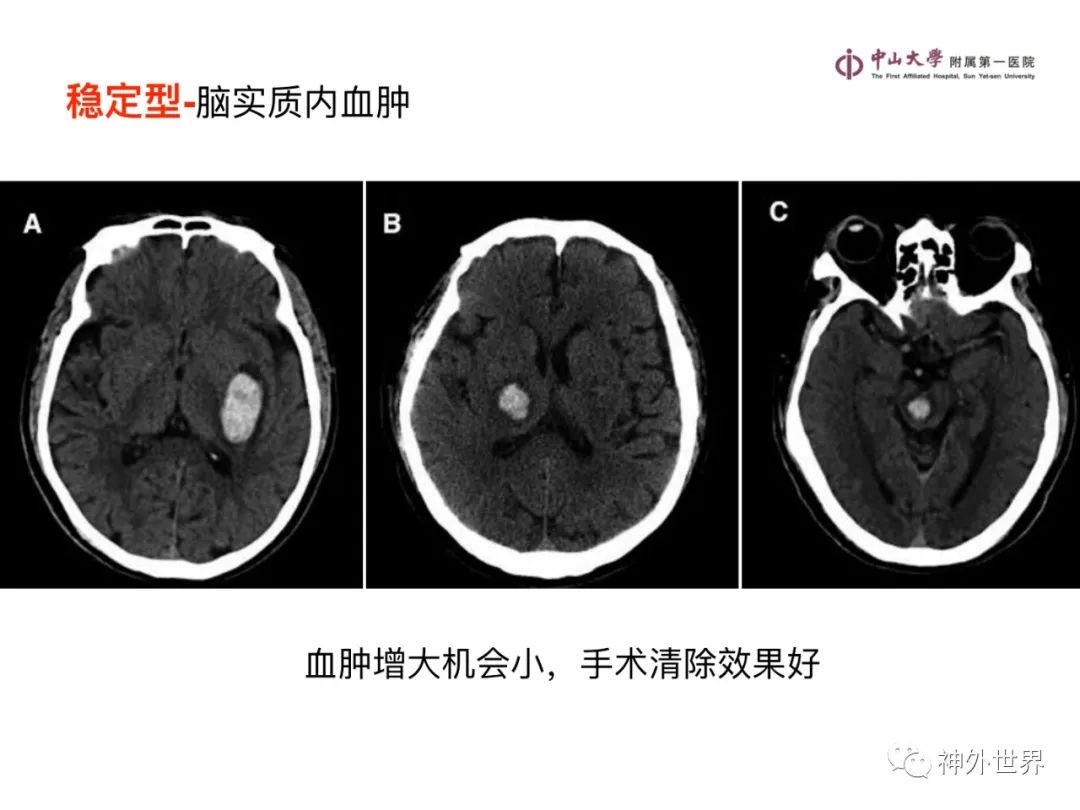

大脑MR、CT 的阅片技巧,超赞 !